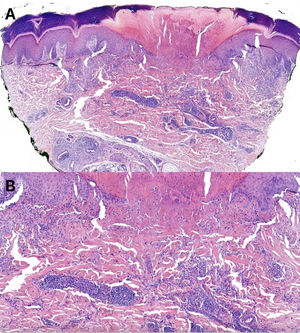

Panoramic microphotography stained with hematoxylin/eosin (H/E, 40×) from a biopsy obtained from a palmar lesion showing a disruption of the epidermis along with localized collagen alteration and an inflammatory infiltrate in the mid and upper dermis. A central keratotic plug was distinctly visible, imparting a cup-shaped contour to the lesion through which collagen was extruded transepidermally. Dermal perforation was evident (A). Histopathologic examination revealed collagen degeneration with necrobiotic features and a perivascular lymphohistiocytic infiltrate. Histiocytes arranged in a palisading pattern surrounded areas of degenerated collagen and mucin deposits (H/E, 200×) (B).